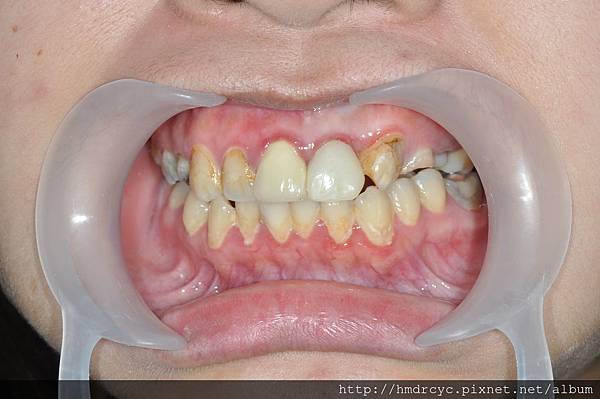

裝上鑄心後牙齒的高度寬度都恢復

假牙也可以穩定的包覆在牙齒上

裝上臨時假牙咬合

門面重建了K小姐也不再擔心

等牙齒製作全瓷牙冠完成後

可以期待恢復功能與美觀性